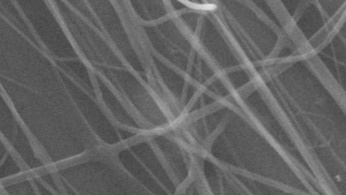

Morphology, size and size distribution of the nanofibres

Morphology analysis was adapted from Aytac et al. (2019) [38]. The SEM analysis was conducted to detect electrospun nanofibers' fibre shape and diameter. The electrospun nanofibres from 18 runs were investigated individually by SEM (FEI, quanta 450, Czech). Images revealed the morphology of resultant nanofibers and measured their diameters in nanometres. The average number of records was calculated using a standard deviation estimation. The setting of the SEM machine was conducted on voltage 25.00 kv, magnification 23624 and width (8.3-9.3 mm).

Results of the SEM analysis are listed in table 2, with a wide range of fibre diameters starting from 87.2 nm (run 13) to 2500 nm (run 18). Run 18 did not produce true nanofibers due to the deficient concentration of PVA. The statistical analysis revealed that the effect of each polymer (factor) on the diameter size of the electrospun nanofiber was vast. Therefore, there is a correlation between factors A, B and C and fibre diameter as expressed in equation 5.

Fig. 3: Nanofibres SEM images with nanofiber diameter frequencies. The PVA, PEO and HPMC were symbolised as V, E and P. Data are given in mean±SD, n=3

The morphology of nanofibers would be affected by device parameters such as flow rate, voltage and distance from the collector. Also, nanofibres' properties could be changed due to temperature and humidity. The bead formation appears with a low concentration of PVA (run 2) or a high concentration of PEO and HPMC (runs 6 and 11), as shown in fig. 3. Therefore, increasing PVA concentration leads to beads' disappearance and smooth fibres' formation. Nageeb El-Helaly (2021) and Silva J. A. et al. (2021) reported similar results [47, 48]. Kalluriet al.(2021)[49] studied the relationship between the fibre diameter, bead diameter and flow rate. Thus, they concluded that better fibre uniformity and bead formation were needed at a high flow rate. These results appear clearly in run two and run six and agree with Silva et al.(2021) results [50], who reported that only the concentration of PVA (≥ 15%) could produce uniform nanofibers when using the lower molecular weight of PVA (67,000). Fibre diameter of 15% PVA and more appeared to be in the range 87.11 to 252.5 nm with uniform fibres and disappearance of beads except in run 6, where the beads appear due to increasing the concentration of HPMC as highlighted by Gripet al. (2018) [46].